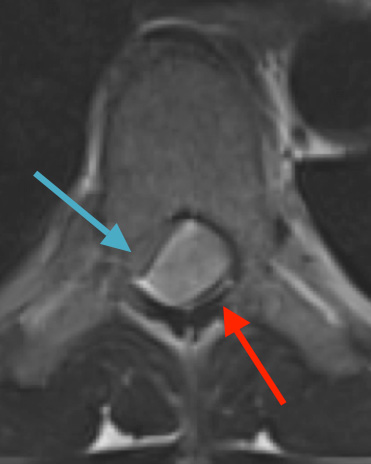

Preoperative MRI T1w demonstrating a large enhancing tumor (red arrow) causing severe cord compression and displacement (blue arrow)

Preoperative MRI T1w demonstrating a large enhancing tumor with severe cord compression